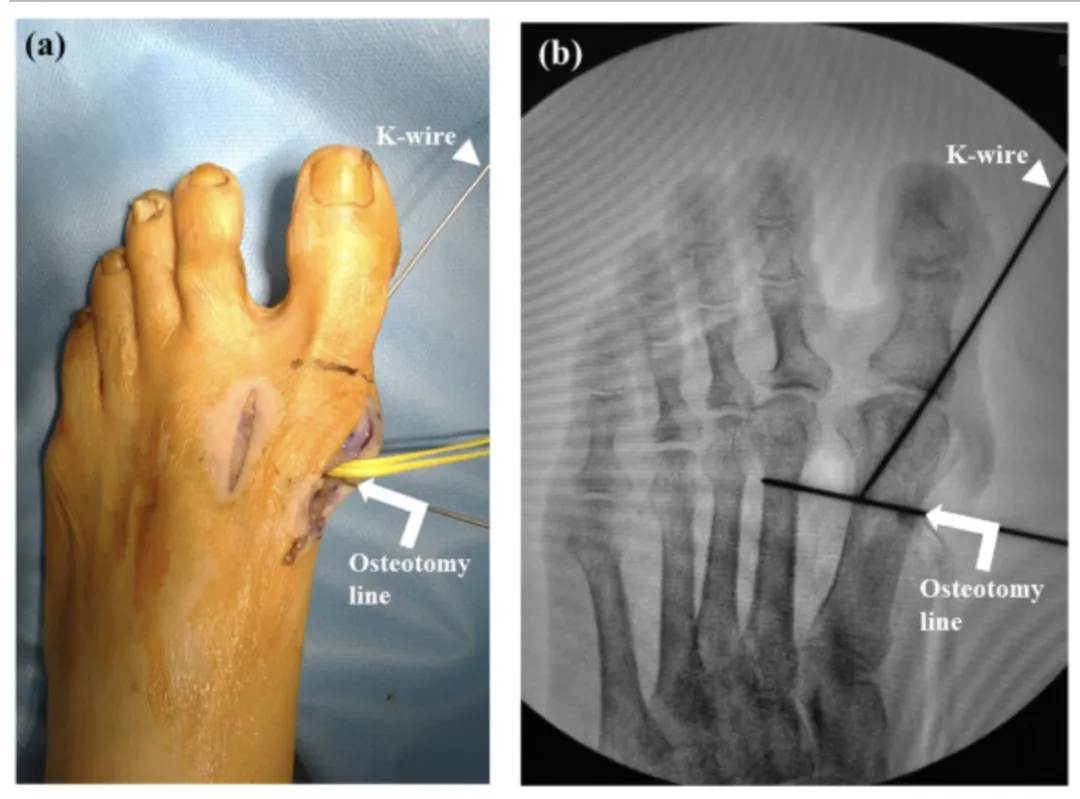

图片来源:Temporary Kirschner wire fixation of the first metatarsophalangeal joint before osteotomy for hallux valgus克氏针在骨科手术中早期主要用于骨牵引术,包括跟骨牵引、胫骨结节牵引、股骨髁上牵引、尺骨鹰嘴牵引等多种情况。然而,随着医学技术的不断进步,克氏针在创伤骨科手术中的用途也得到了进一步拓展。如今,它在骨折复位后以及接骨板的临时固定中发挥着重要作用。有时,克氏针还可以作为导针使用,便于置入其他内固定物,如空心螺钉、Herbert螺钉等,为手术操作提供了极大的便利。